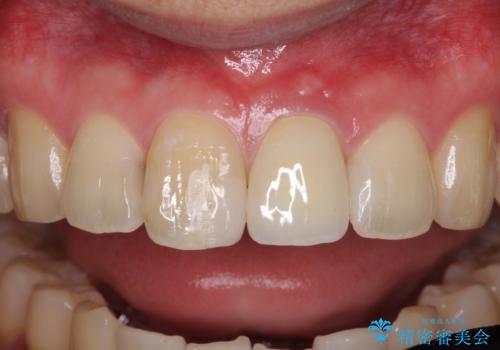

歯髄は既に壊死していたため、根管治療を行い、その後オールセラミッククラウンにて補綴することとしました。

変色による周囲に視線が気にならなくなり、明るいくらいとなりました。